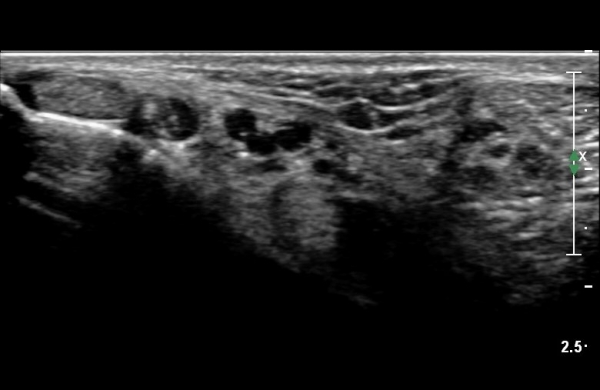

ŽÃËÀÚ¸¦ Á¶±Ý ´õ À̵¿ÇÏ´Ï ³¶Á¾ÀÌ ¿ÜÃøÁ·Àú½Å°æ Ç¥ÃþÀ¸·Î À§Ä¡ÇÑ´Ù. ½Å°æÀÇ ½ÉÃþ¿¡¼­´Â

±ä¾öÁö±¼°î°ÇÀÌ º¸ÀδÙ(»çÁø 4, 5).